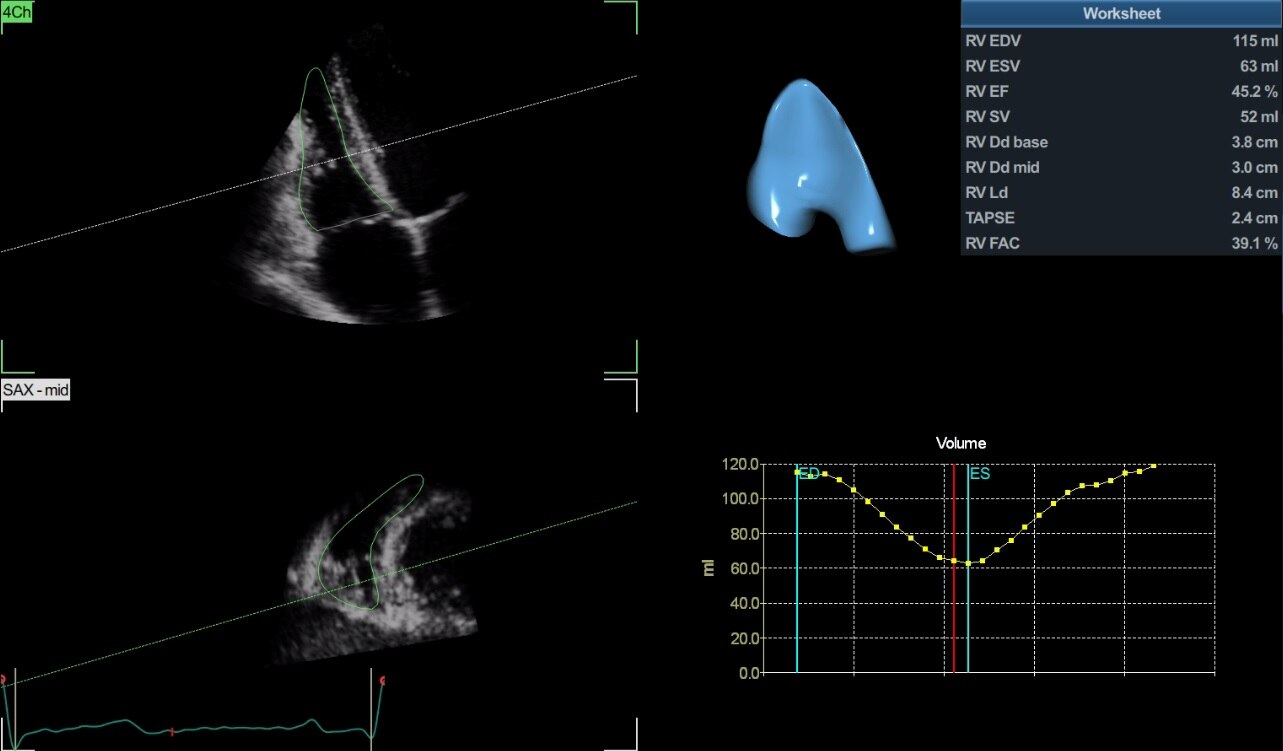

4D Auto RVQ*